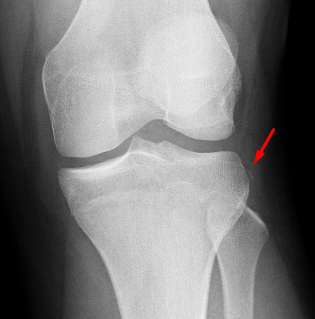

Age: 17

Sex: Male

Indication: Knee injury

Sample ReportAcute avulsion fracture along the lateral tibial plateau (Segond fracture) and impaction fracture of the lateral femoral condyle, both of which are associated with ACL tears. Recommend knee MRI for further evaluation.

Mild lateral patellar tilt.

Moderate-sized joint effusion.